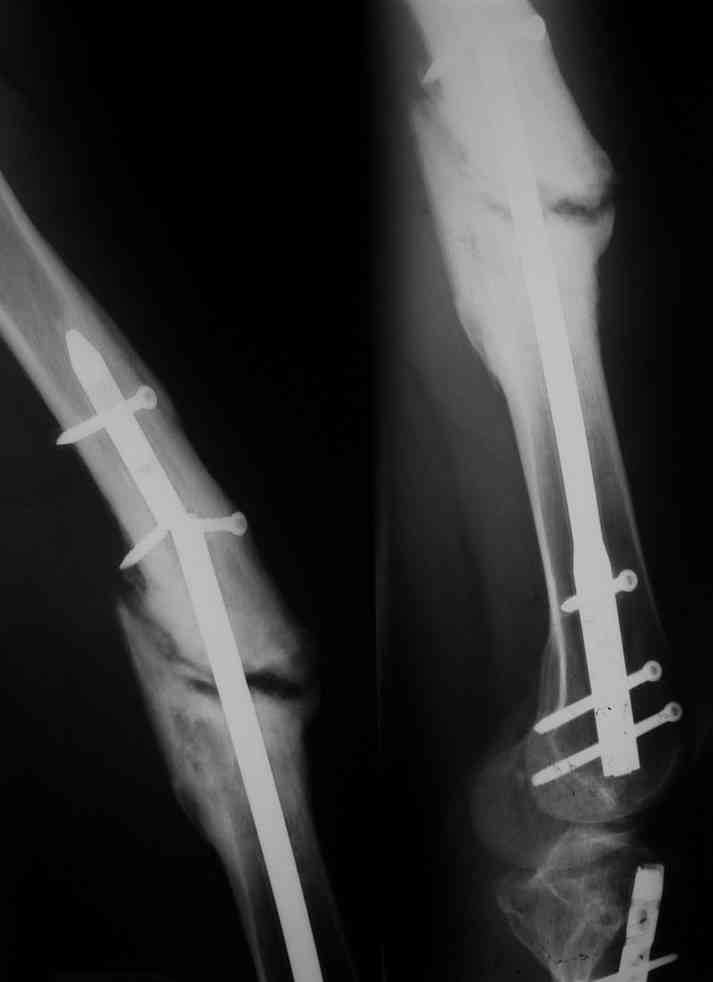

Одной рентгенограммы недостаточно, чтобы планировать подобную операцию. Вот похожий

случай, который пришлось оперировать 3 мес. назад. Тоже короткий гвоздь. Шляпки винтов

проксимального фрагмента полностью погружены в костную ткань, чего уже достаточно для

необходимости обнажения этой зоны. У этого же больного оказались полностью разрушены шлицы

2-х дистальных винтов, так что и там нужно было "открываться".